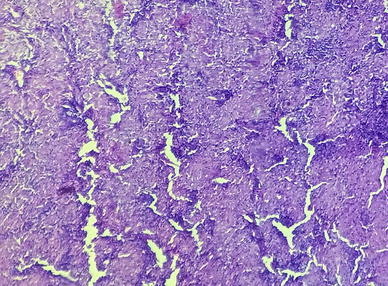

Fig. 7.

Low magnification histopathology showing dilated sinuses distended with benign histiocytes

Fig. 8.

High magnification histopathology showing dense lymphocytic infiltrate

A fifteen year old boy was presented to our hospital with chief complaints of painless progressive swelling in the right side of neck in last 6 months. Patient was having no history of fever, pain in throat, difficulty in deglutition, difficulty in respiration, chronic cough, loss of appetite or loss of weight. On examination there was non-tender, non-fluctuant soft to firm swelling involving anterior and posterior triangle of neck about 10 × 6.5 cm in dimension on right side. It was mobile and not adherent to underlying skin (Figs. 1, 2). There was also swelling involving bilateral supraclavicular region. There was no any swelling in axillary or inguinal region. On nasal endoscopy no abnormality was detected. Routine haematological examination showed Haemoglobin 12.2 g%, Total leukocyte count 6.3 × 109/litre, Erythrocyte sedimentation rate 15 mm 1st hour while differential leukocyte count was with in normal limits. Mantoux test was negative. High resolution Ultrasonography suggested multiple discrete, homogenous lymph node in right carotid space. There was no cystic necrotization, calcification or loss of fibrofatty plane are seen (Fig. 3). Contrast enhanced computed tomogram neck with thorax suggested a large lobulated soft tissue lesion about 10 × 6.5 × 5.5 cm in dimension (Fig. 4). No intratumoral necrosis was seen. Patchy heterogeneous enhancement was seen in post contrast images. Mass was mildly compressing trachea and right thyroid gland to the left (Figs. 5, 6). Bilateral supraclavicular lymph node was seen along with non-necrotic lymph node in superior mediastinum. Fine needle aspiration cytology from cervical lymph node was highly suggestive of Rosai–Dorfman disease, however biopsy was advised for confirmation. Biopsy was done under local anaesthesia from the posterior triangle of neck just behind the mid part of sternocleidomastoid muscle. Histopathology showed diffuse effacement of lymph node architecture and dilated sinuses distended with benign histiocytes (Figs. 7, 8); the diagnosis was given as sinus histiocytosis with massive lymphadenopathy (Rosai–Dorfman disease). This patient was put on oral prednisolone 10 mg three times a day in tapering doses for 21 days initially and then on low dose of steroids for next 4 months. The patient showed marked clinical improvement.